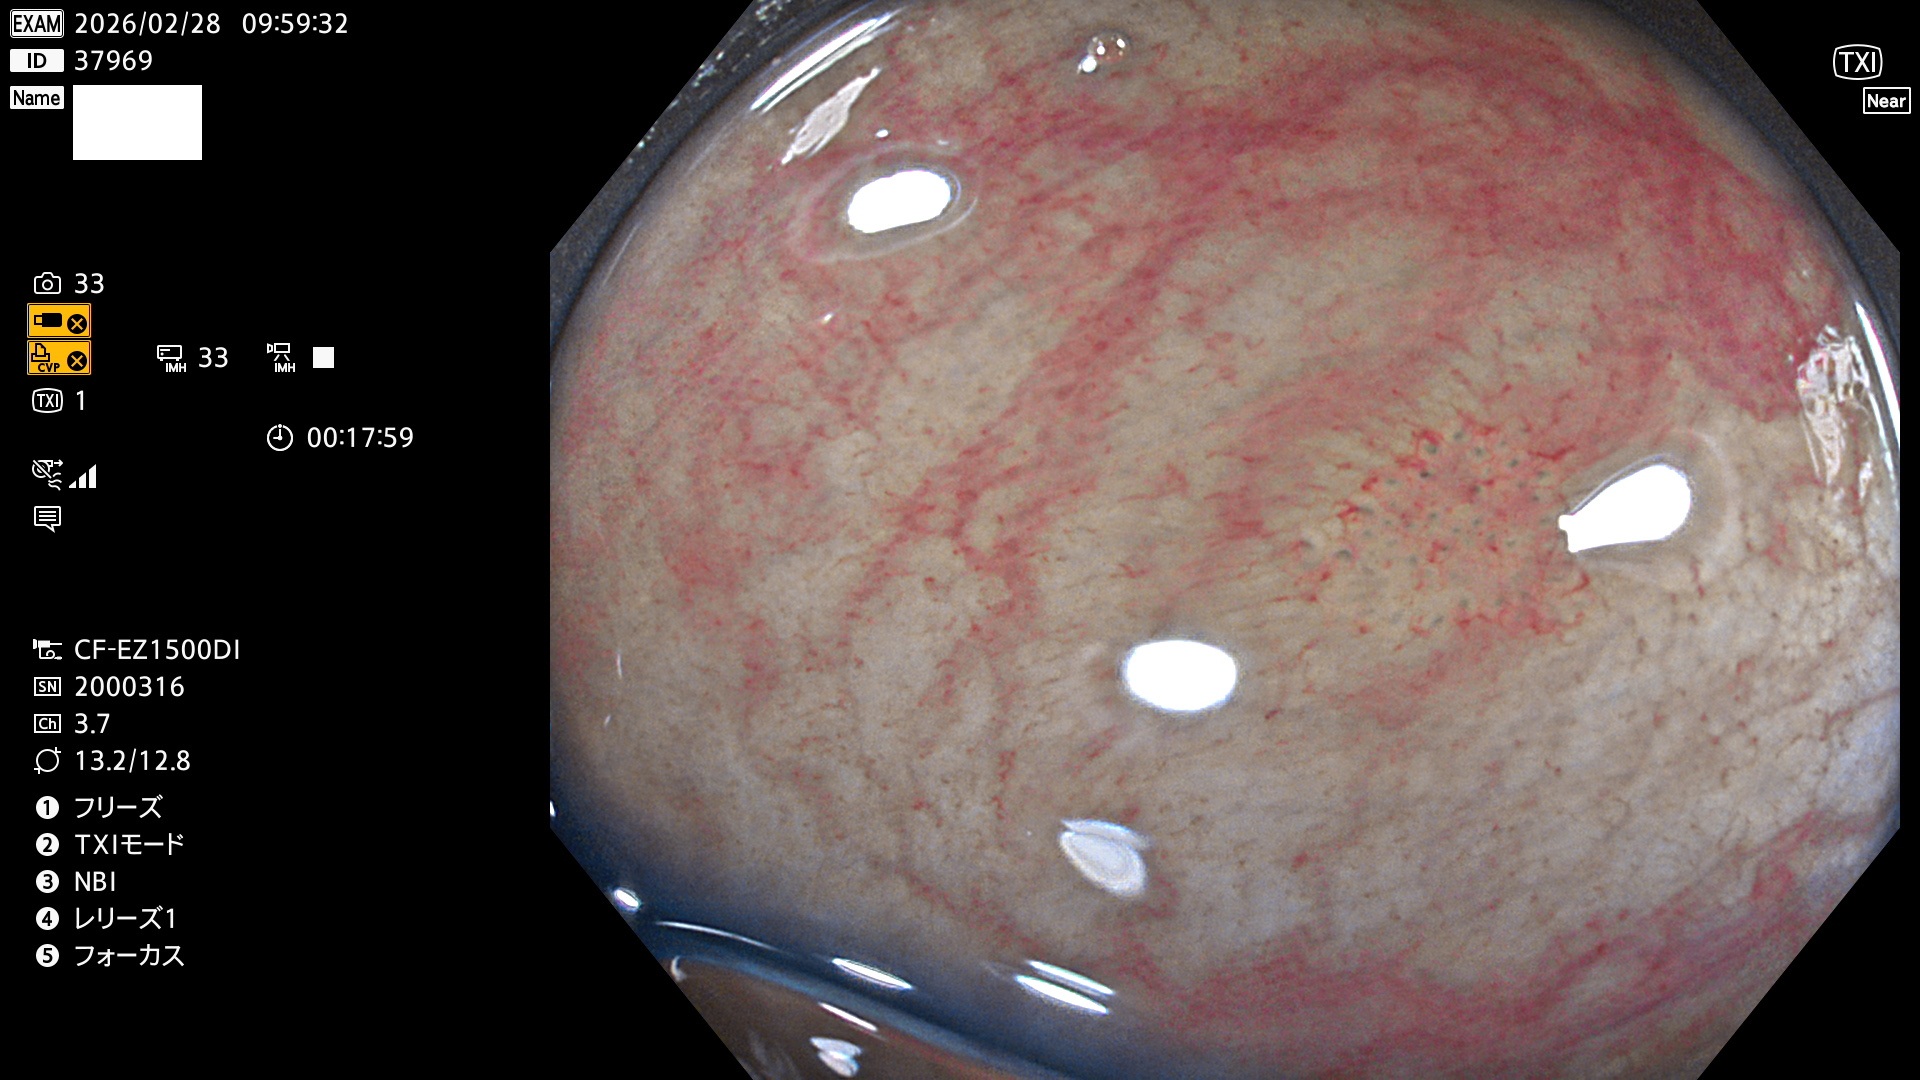

完全に平坦な物をUb、陥凹している物をUcと呼びます。Ubは認識が困難で、Ucはびらん(炎症)と紛らわしいために見落とされやすく、「内視鏡後・大腸癌」の原因になります。

専門的)Uc=De Novo癌? 内視鏡の解像度が低かった時代、このような説もありました。しかし今日の高精度内視鏡では良性の微小なUc型腺腫(APC遺伝子異常の腺腫)が日常的に見つかります。Ucこそが多段階発癌(Adenoma-Carcinoma Sequence)のMain Routeです。

毎週の検査(木・金・土・日)に発見されたUbとUc型・腺腫を、その週の日曜の夜にUPし1週間、提示します。

2026年2月26日〜3月1日の4日間(40件)2個 (Uc_ADR=2個/40人=5%)